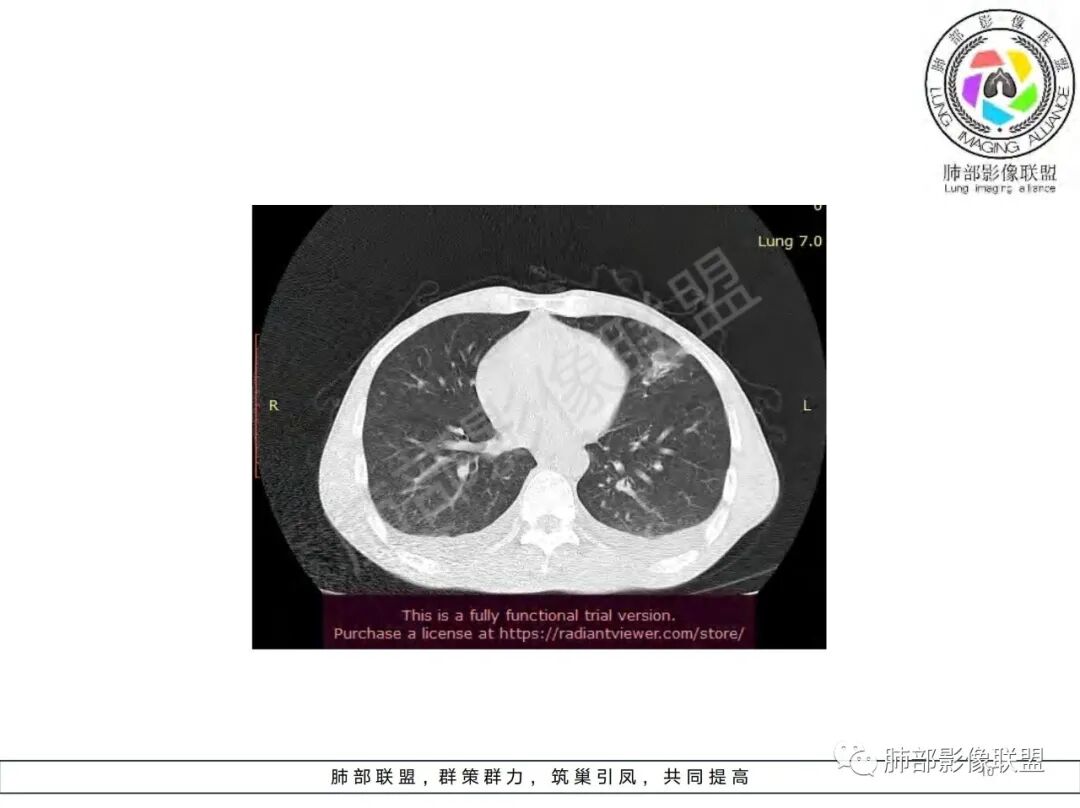

双肺多发大小不等结节影,边缘伴有磨玻璃影,边界欠清,部分与血管束相连,支气管似有穿行病灶内,结节有融合,左肺下叶厚壁空洞,伴有反晕征,左侧胸水,临床中年男性,发热40℃,CRP增高,感染性病变,1:类鼻疽伯克霍尔德菌(好发海南,影像表现也符合)

影像:双肺多发结节、实变影,大部分病灶边界不清,分布相对随机,左下肺坏死空洞形成,伴左侧胸水。

影像表现:双肺弥漫分布斑片影、实变影、磨玻璃影、结节影,晕征、反晕征,随机分布,部分病灶空洞形成前兆,左侧胸腔积液。

影像表现:双肺多发结节、实变影,大部分病灶边界不清,随机分布趋势,左下肺“反晕征”,似有形成空洞趋势。左侧胸腔积液。治疗后复查 ,大部分病灶吸收好转,呈较为典型血播分布,肝脏低密度块影,边界不清,符合肝脓肿。